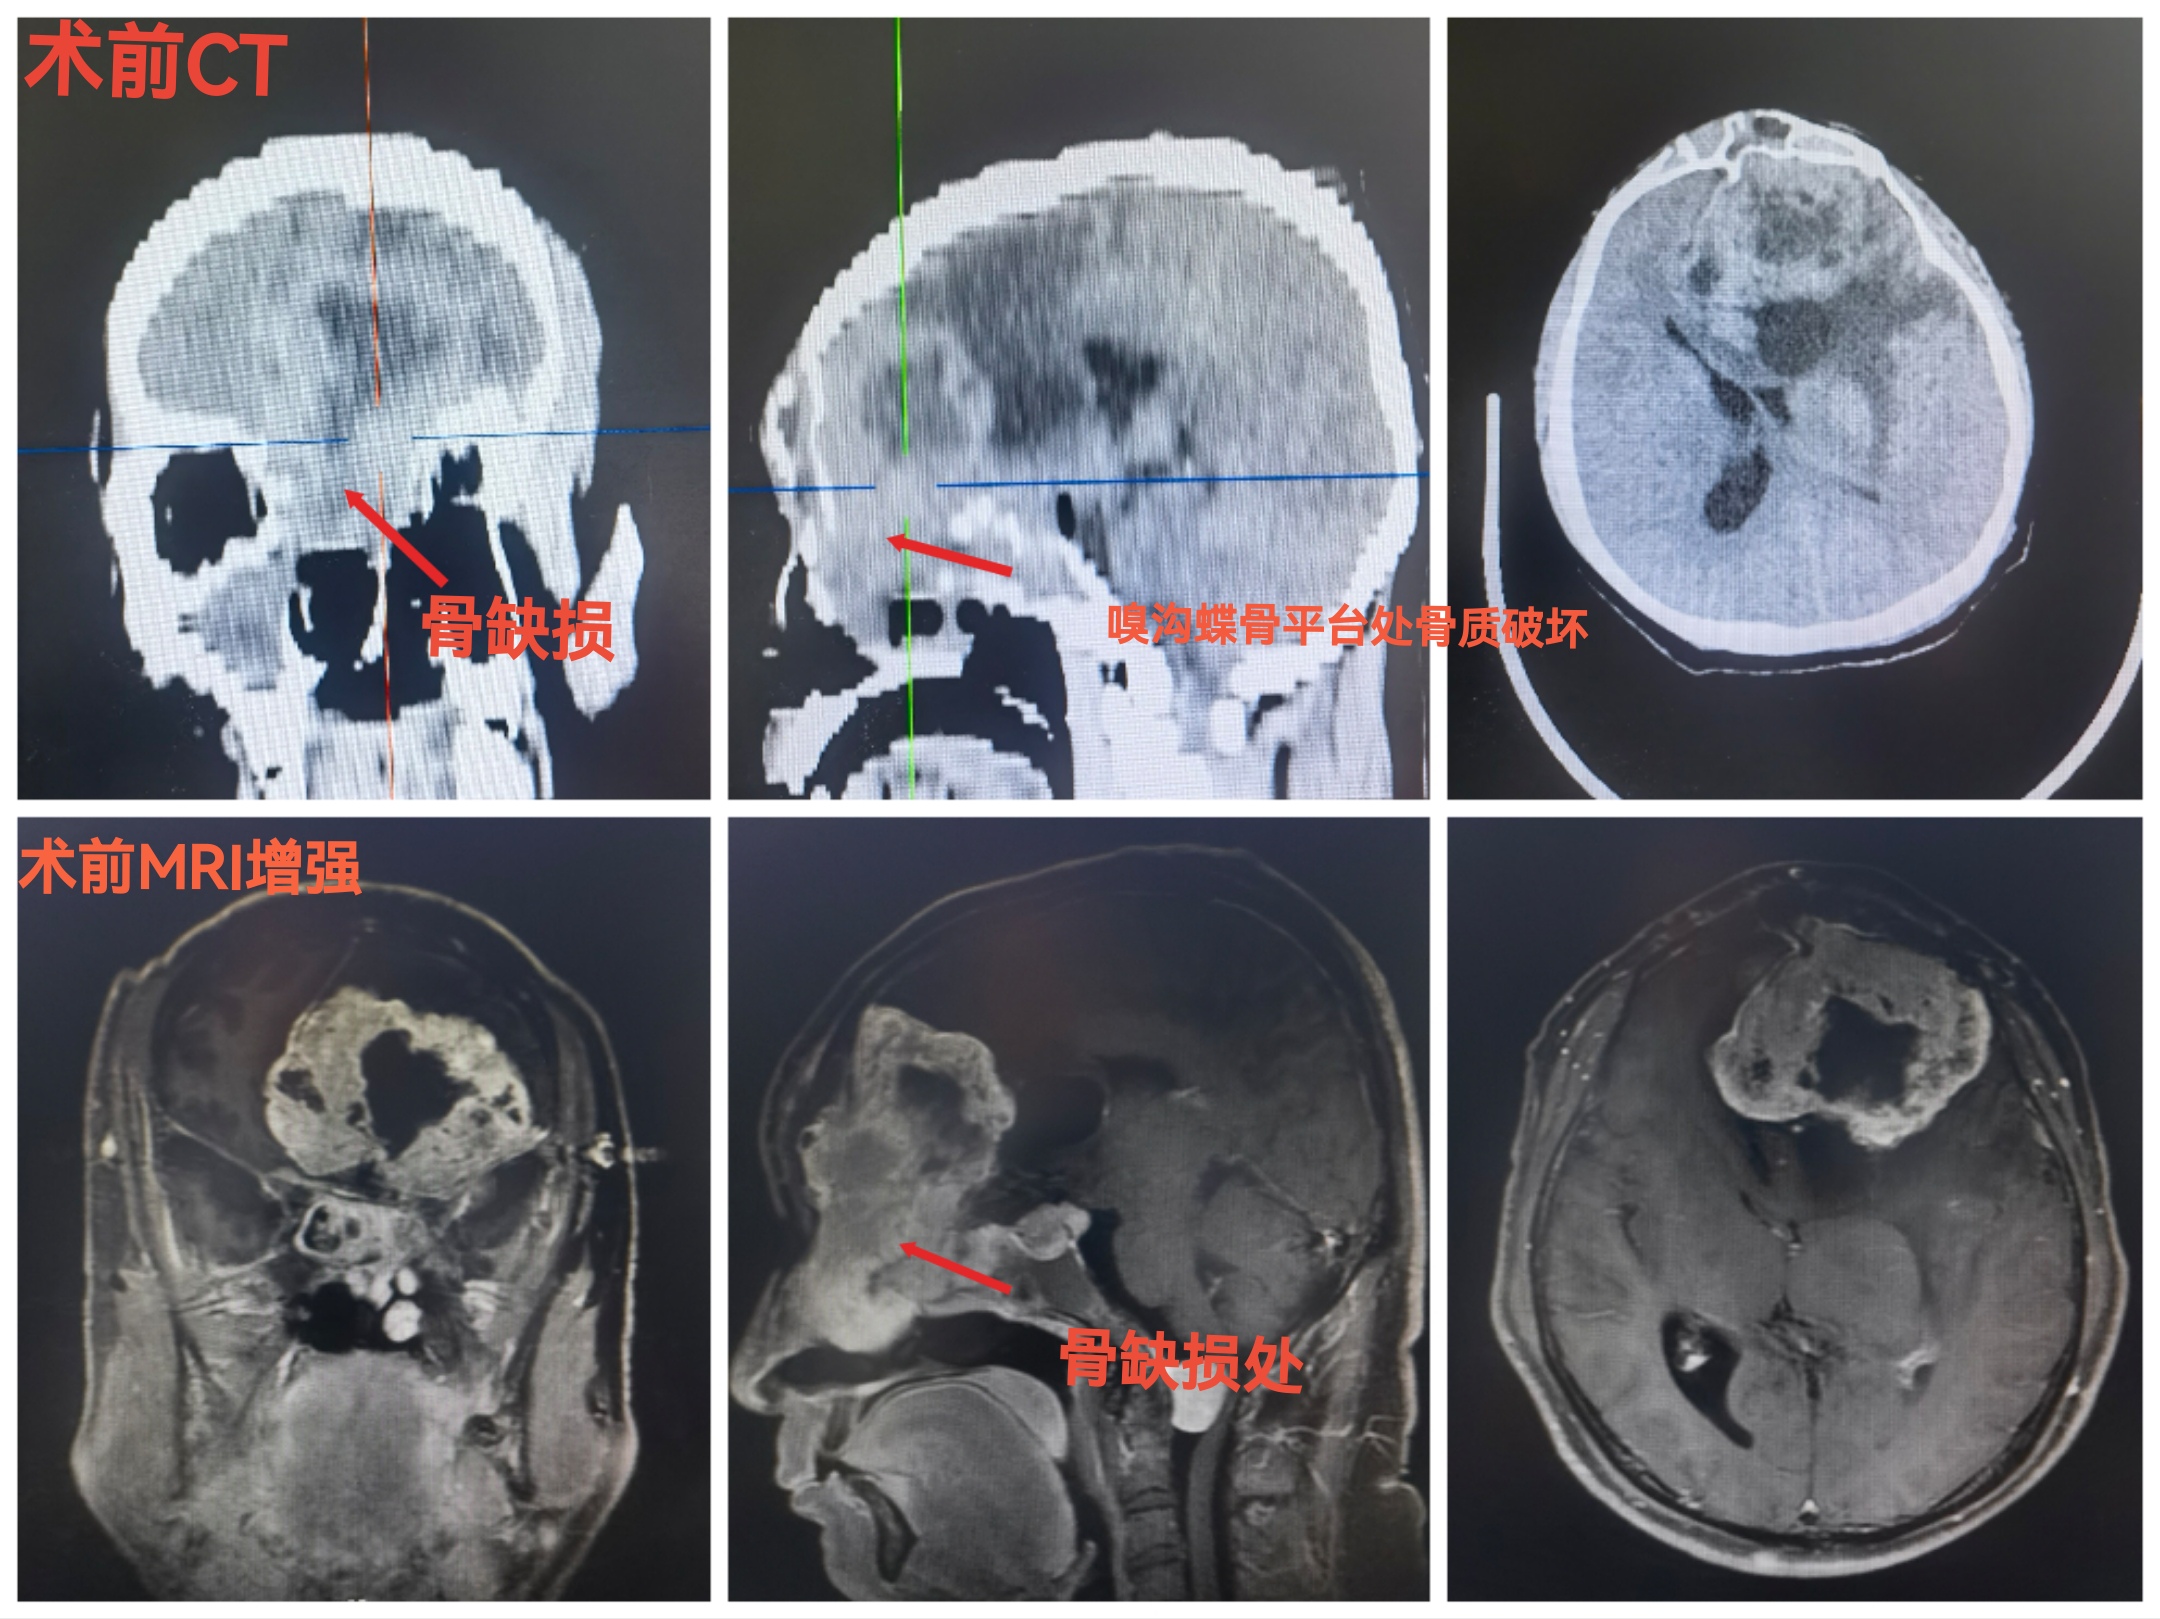

CT扫描可见颅内等密度占位,局部水肿明显,中线向右偏移。冠状位重建可见嗅沟蝶骨平台处骨质破坏导致缺损。

MRI可见肿瘤巨大,中鼻道以上,蝶窦筛窦及双侧额底均为肿瘤组织占据,向两侧到蝶骨嵴。肿瘤分叶状,可明显增强,核心区有坏死。后部可见粗大的静脉。双侧大脑前动脉位于肿瘤的后部。

CT提示颅内肿瘤,前颅底等密度为主。周边水肿明显。占位效应造成中线移位。

肿瘤侵及颅鼻眶

肿瘤向后到鞍结节前床突,向外到两侧的蝶骨嵴。

CT与增强MRI的对比